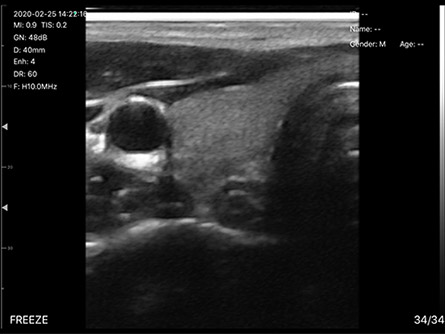

- 显示模式:B、B/M,彩超版本有CF、PW、PDI

彩超(白色头192阵元/藏蓝头128阵元)、高配黑白(浅蓝头128阵元)、低配黑白超(灰头80阵元)

7.5/10MHz(声头40mm宽)、10/14MHz(声头25mm宽),和带导针架固定装置的PICC专用等型号

日常检查:甲状腺、乳腺、脂肪肝/肝硬化、盆底盆腔、前列腺、脑卒中筛查、眼球视网膜动脉、子宫及附件、卵巢卵泡监测、查环查孕、胎儿扫查、肌骨、足底、骨折判断、静脉曲张、肝肾脾、膀胱/泌尿功能、尿量测算等